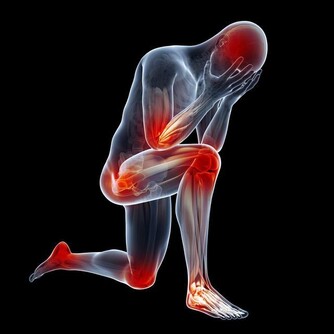

這種坐姿影響跳躍、投擲和踢腿等動作。當小孩以「W型坐姿」坐在地上時,膝蓋是向外翻,這種姿勢會導致孩子的髖外展肌、股後肌群、內轉肌和跟腱承受更大的壓力,還會影響孩子背部及盆骨的發育,導致孩子形成內八。

說這種普遍的坐姿其實對兒童相當的危險,父母們應當盡量去矯正他們的這種坐姿。當孩子以「W型坐姿」開腳的坐在地上時,他們的膝蓋向外翻,將腳塞在最下面。這種姿勢對小孩的生長髮育方式有一定的負面影響。很多運動能力都與平衡性有關,採用「W型坐姿」會抑制人體在兩側的平衡能力的發展。

更糟的是,很多專家認為這種坐姿與發育遲緩有一定的聯繫。這種看似舒服的姿勢會給髖外展肌 (hip abductors)、股後肌群 (hamstrings)、內轉肌 (internal rotators)、跟腱 (heel cords)帶來額外的壓力,長時間以這種方式坐著,雙腳可能會內撇和足弓反轉,影響步行姿勢,嚴重更會引致「脊柱前凸」,即脊柱大幅向內彎曲,影響身體整體的平衡感和協調能力。最終你可能不得不去醫院看骨科。

坐成 「W型坐姿」時,孩子自然無法挺直脊椎,脊椎大幅向內彎曲,背肌的功能也會因此會削弱,更會影響身體整體的平衡感和協調能力。